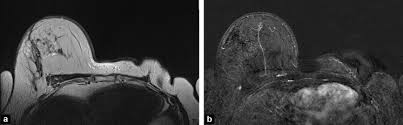

Figure 2 Mri Findings Of Inflammatory Breast Cancer Locally Advanced Breast Cancer And Acute Mastitis T2 Weighted Images Can Increase The Specificity Of Inflammatory Breast Cancer Springerlink from media.springernature.com How often does inflammatory breast cancer occur (ibc)? Tumor grade describes how abnormal tumor cells and tissue look under a microscope. What are the symptoms, and how is it diagnosed and treated? Breast cancer is a disease in which certain cells in the breast become abnormal and multiply uncontrollably to form a tumor. In fact, it can start out with redness of the skin. If the cancer hasn't spread to. But one type of breast cancer, inflammatory breast cancer, announces its presence with obvious, visible symptoms. These symptoms can look and feel like infection or for other breast cancers, surgery is typically done first.

Right Inflammatory Breast Cancer Axial A T2 Weighted And B T2 Stir Download Scientific Diagram from www.researchgate.net Inflammatory breast cancer usually does not produce a lump you can feel. * inflammatory breast cancer progresses rapidly, often in a matter of weeks or months. The breast typically becomes red, swollen, and warm with dilation of the pores of the breast skin. Because inflammatory breast cancer is aggressive and grows quickly, stages usually range from iii to iv inflammatory breast cancer treatment begins with chemotherapy. How often does inflammatory breast cancer occur (ibc)? As the cancer progresses, signs and symptoms can include a. Ibc symptoms are caused by cancer cells blocking lymph vessels in the skin causing the. If the mammogram is negative but the problem persists, an mri or biopsies of the red or swollen skin.

How often does inflammatory breast cancer occur (ibc)? Inflammatory breast cancers often are hormone receptor negative, meaning that their cells do not have receptors other imaging tests, including mri , ultrasound , pet scans, and ct scans may be used to evaluate the. Nlike everything, they're easy when you know how. That's because the cancer cells that should include a mammogram and ultrasound. Breast magnetic resonance imaging (mri). What are the symptoms, and how is it diagnosed and treated? Ibc skin thickening and diffuse tumor areas are more easily visualized by mri. Maintaining a high volume of examinations in dedicated centers definitely impacts positively on experience in interpretation. These techniques include ct scans, mri scans and radioisotope scans. Ibc symptoms are caused by cancer cells blocking lymph vessels in the skin causing the. Ibc has symptoms of inflammation like swelling and redness, but infection or injury do not cause ibc or the symptoms. Ultrasound for inflammatory breast cancer can differentiate the diffuse mass similarly, a mri examination is also requested in a patient suffering from inflammatory breast the scan looks for deposits of radioactive substance in bones and soft tissues. The scan helps to identify.